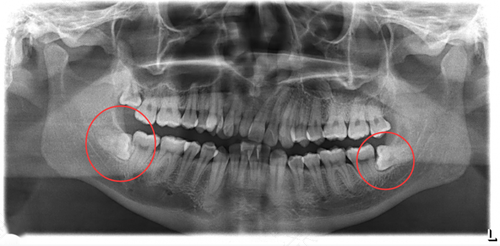

智齿就是多长出来的牙齿,这个牙齿如果没有出现病变,或者是没有阻碍到其他牙齿的话,可以不拔除。但是如果影响到了其他的牙齿,或者是出现虫牙的话,需要马上拔除。拔牙需要到正规的医院,避免出现感染。那么,拔智齿是否需要缝线呢?

如果智齿已经完全长出来了,这种情况下拔除的话,不需要缝线,只需要服用一些消炎的药物就可以了。如果智齿还没有长出来,还在牙龈里面,想要拔除的话,需要切开牙龈,这种情况下拔除伤口会比较大,需要缝线,还需要做好消炎的措施。